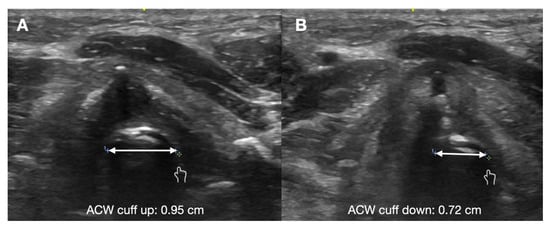

7. Assessment of Laryngeal Edema

- Mikaeili, H.; Yazdchi, M.; Tarzamni, M.K.; Ansarin, K.; Ghasemzadeh, M. Laryngeal ultrasonography versus cuff leak test in predicting postextubation stridor. J. Cardiovasc. Thorac. Res. 2014, 6, 25–28. [Google Scholar]

- El Amrousy, D.; Elkashlan, M.; Elshmaa, N.; Ragab, A. Ultrasound-Guided Laryngeal Air Column Width Difference as a New Predictor for Postextubation Stridor in Children. Crit. Care Med. 2018, 46, e496–e501. [Google Scholar] [CrossRef]

- Ding, L.W. Laryngeal ultrasound: A useful method in predicting post-extubation stridor. A pilot study. Eur. Respir. J. 2006, 27, 384–389. [Google Scholar] [CrossRef] [PubMed]

- El-Baradey, G.F.; El-Shmaa, N.S.; Elsharawy, F. Ultrasound-guided laryngeal air column width difference and the cuff leak volume in predicting the effectiveness of steroid therapy on postextubation stridor in adult. Are they useful? J. Crit. Care 2016, 36, 272–276. [Google Scholar] [CrossRef]

- Bhargava, T.; Kumar, A.; Bharti, A.; Khuba, S. Comparison of Laryngeal Ultrasound and Cuff Leak Test to Predict Post-Extubation Stridor in Total Thyroidectomy. Turk. J. Anaesthesiol. Reanim. 2021, 49, 238–243. [Google Scholar] [CrossRef] [PubMed]

- Tsai, W.W.; Hung, K.C.; Huang, Y.T.; Yu, C.H.; Lin, C.H.; Chen, I.W.; Sun, C.K. Diagnostic efficacy of sonographic measurement of laryngeal air column width difference for predicting the risk of post-extubation stridor: A meta-analysis of observational studies. Front. Med. 2023, 10, 1109681. [Google Scholar] [CrossRef] [PubMed]